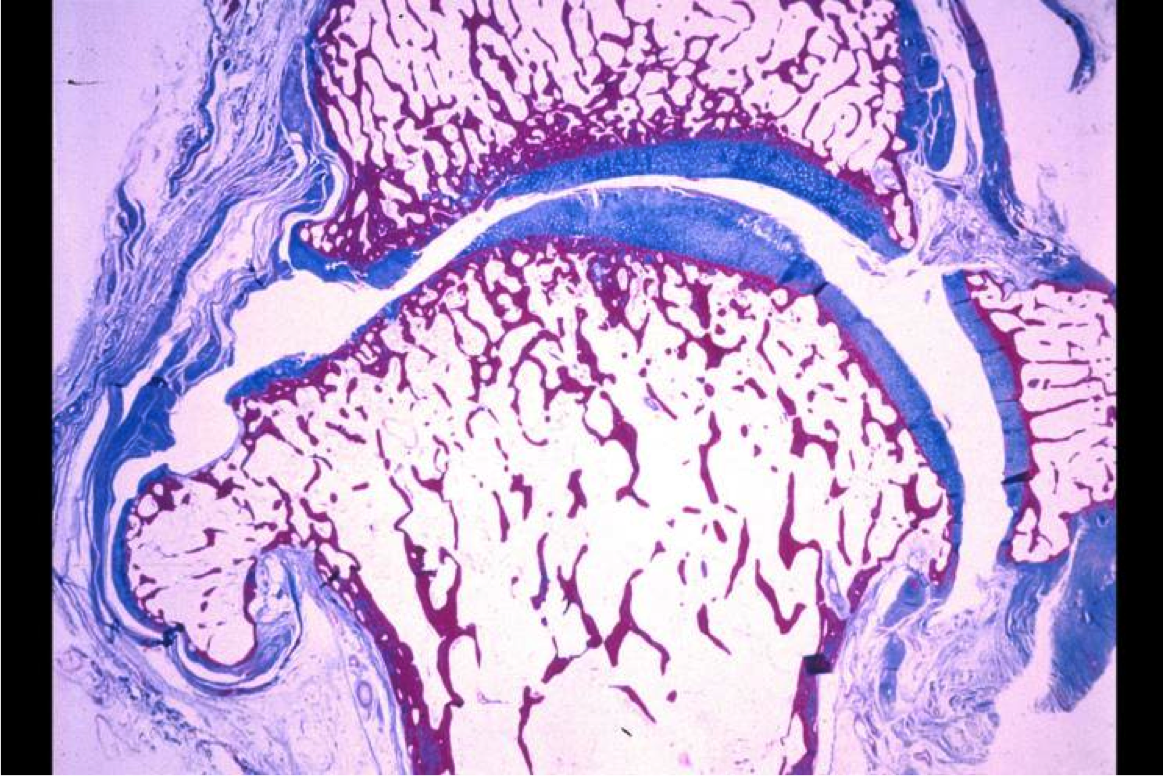

RA is a disease of what part of the joint?

the synovium. synovium proliferates (almost tumor-like)

OA is a disease of what part of the joint?

cartilage. wears away over time

Articular/hyaline cartilage: what is the main purpose? general qualities? what is it made of?

what lies directly beneath articular/hyaline cartilage?

subchondral bone

what happens to cartilage in early OA? (grossly)

what happens to cartilage in early OA, at the histological level?

Later in OA progression: what happens to cartilage? bone? infiltrates? other structures?